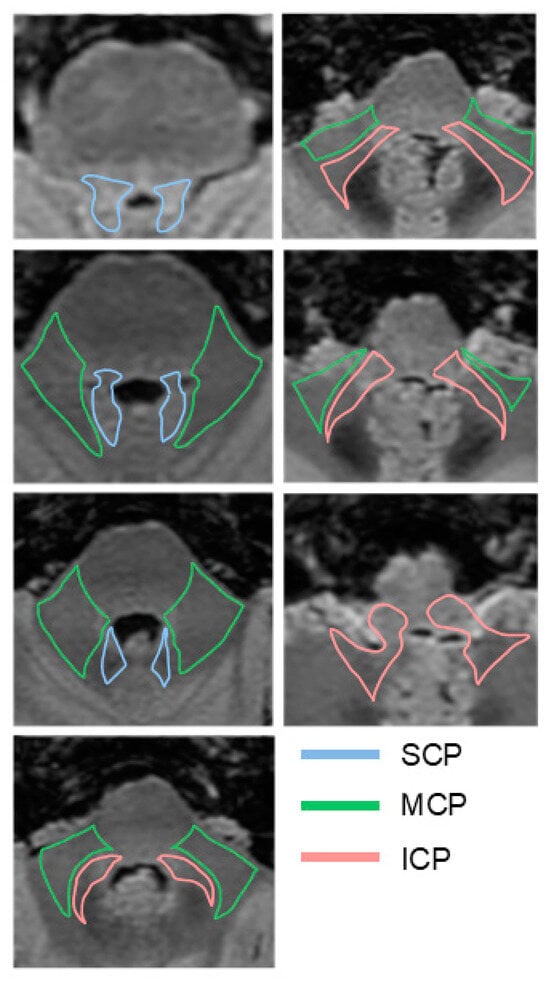

- Diffusion MRI and tractography: Diffusion MRI is a relatively new MRI technique that allows for the study of white matter microarchitecture. Tractography is a 3D visualization technique to reconstruct white matter fiber tracts using data collected by diffusion MRI. It enables the visualization of cerebellar tract directionality and decussation and allows the calculation of FA, a key metric that quantifies the directional coherence of water diffusion within a voxel. FA ranges from 0 (isotropic, random diffusion) to 1 (anisotropic, organized tracts). However, FA does not solely reflect integrity—crossing fibers in a voxel can lower FA despite intact tracts, while high FA might reflect loss of one fiber tract, not improved health. Complementary DTI metrics help refine interpretation [80]. A high angular diffusion data acquisition scheme, such as High Angular Resolution Diffusion Imaging (HARDI), together with multicompartment orientation reconstruction methods, such as the multi-shell multi-tissue spherical deconvolution method [81], can resolve multiple intravoxel fiber orientations and are particularly useful in regions with crossing fibers, where traditional diffusion tensor models (assuming a single fiber population per voxel) fall short in capturing the underlying macrostructural tissue complexity [82,83,84].

- Peduncular width: Some studies have reported average values in healthy population measured in T1-weighted sequences. For individuals with a median age of 60.75, with standard deviation (SD) of 9.95 (n = 61), or older (n = 48), the SCP should be measured in the coronal plane, with normal values of 5.09 ± 0.82 mm (SD) or in the axial plane at the level of the inferior colliculus (2.2 ± 0.46 mm). The MCP should be measured in parasagittal slices (9.61 ± 1.1 mm) or in the axial plane at the level of the trigeminal nerve (13 ± 1.8 mm). The ICP should be measured in the axial plane at the level of the connection between the cerebellum and the medulla (5 ± 0.12 mm) [8,86].